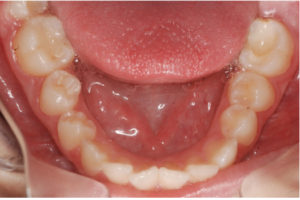

Documento utilizado en todo procedimiento odontológico y en cualquier especialidad, consiste en una secuencia de fotos faciales y dentales en diferentes ángulos, que permiten un diagnostico ideal y evaluar los avances del tratamiento al tener fotos posteriores, además es un documento legal.